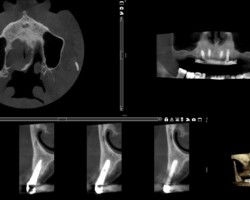

Avant-Après :